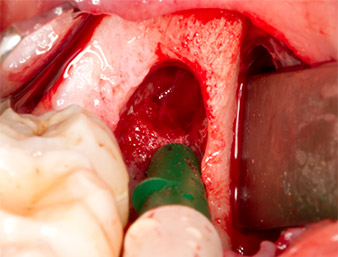

En la imagen en 3D (tomografía volumétrica digital) se constató que el resto radicular se encontraba muy desplazado en sentido distocaudal en la transición situada entre la porción horizontal y la ascendente del maxilar inferior (figura 2).

TVD transversal

Imagen 2: Representación de una TVD transversal del resto radicular en el espacio retromolar.